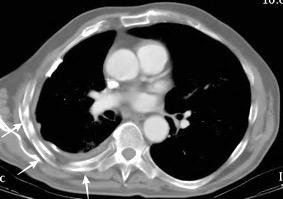

Tromboembolismo pulmonar.

Frecuencia del derrame:

Rx: 32%. TC: 47%

Unilateral. 85%

< 1/3 del hemitórax: 90%

Todos exudados

58% con eritrocitos

21% tabicación lo que causa demora en el diagnóstico

TEP. Empiema pleural. Atelectasia redonda

Porcel JM et al. Analysis of pleural effusions in acute pulmonary embolism: radiological and pleural fluid data from 230 patients. Respirology 2007/ Iguchi T et al. Desquamation of the subpleural lung parenchyma caused by empyema after pulmonary embolism: A case report. Respirol Case Rep. 2022 .